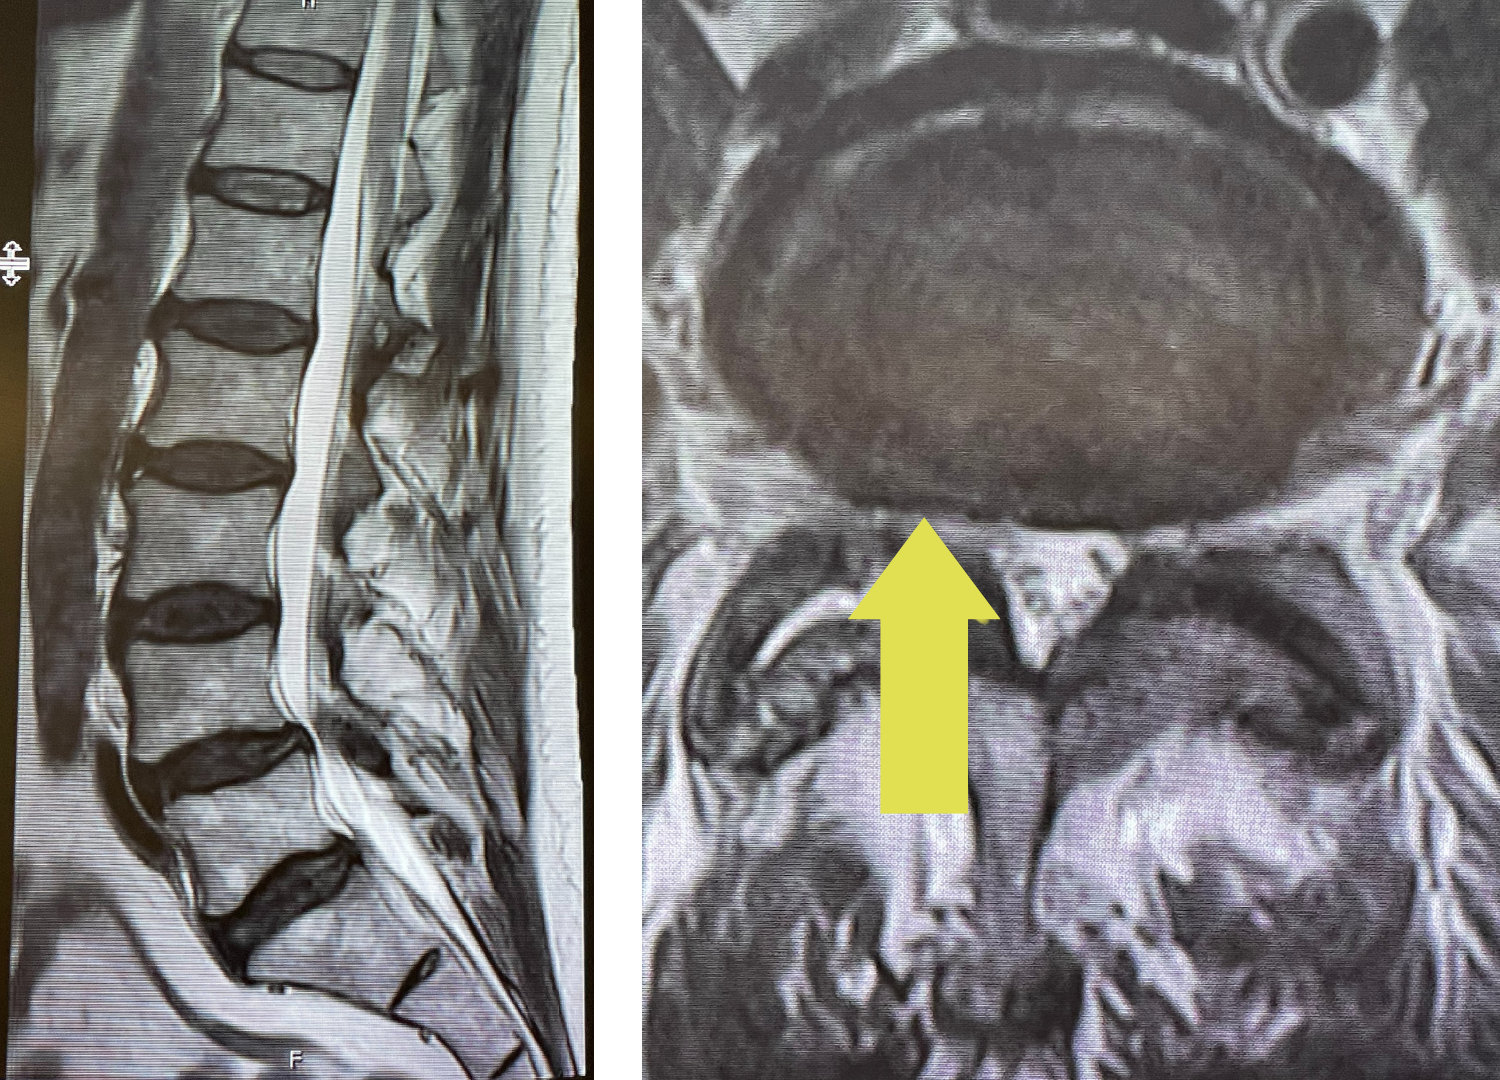

IMG 5090 768x1024 1

Figure 1: Sagittal x-ray after C6-7 anterior cervical discectomy showing collapse of the C5-6 disc space with fully connected anterior bridging osteophyte and C4-5 partially bridged anterior osteophyte with anterior angulation of C4 vertebral body. Sagittal T2-weighted MRI showing listhesis of C4 on C5 with C4-5 disc protrusion causing cord compression.

On the initial visit she was completely neurologically intact. We recommended physical therapy and ordered cervical x-rays and MRI (Fig 1). It appeared on her x-rays that she had a stable C6-7 fusion segment, but she also had a very collapsed C5-6-disc space. In front of that C5-6 disc space there is an obvious anterior osteophyte bridging the space, in essence autofusing that segment. Right above that at the C4-5 space there was an anterior bridging osteophyte as well with some C4 anterior angulation and listhesis with respect to C5, although the bridging bone did not completely bridge across to C5. Since C6-C7 and C5-6 were essentially non functional, there was biomechanical stress on the next segment, C4-5, which resulted in premature degeneration and instability. This also on MRI caused more stress on the C4-5 disc segment and secondary protrusion with anterior cord distortion. Given this was only a static picture of her spine, imagine how her cord is affected on flexion and extension movements.